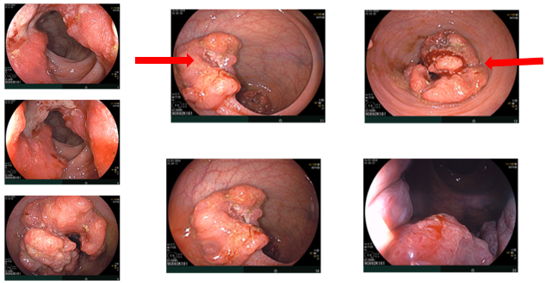

Nội soi đại–trực tràng (07/2024):

Ghi nhận hai tổn thương u sùi ở trực tràng, cách rìa hậu môn khoảng 5 cm và khoảng 10 cm. Tổn thương “phía trong” chiếm gần hết lòng trực tràng; tổn thương “phía ngoài” kích thước khoảng 3,0 cm. Ống hậu môn có đám tổn thương gồ ghề loang lổ.

Hình 1: Tổn thương u sùi ở trực tràng

Hình 2: Tổn thương gồ ghề loang lổ ở ống hậu môn

Giải phẫu bệnh (sinh thiết):

-         Trực tràng: ung thư biểu mô tuyến biệt hóa vừa.

-         Hậu môn: u tuyến ống, loạn sản độ thấp (tubular adenoma, low-grade dysplasia).